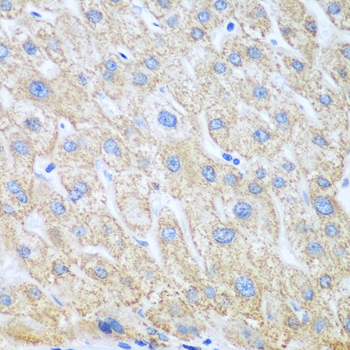

Immunohistochemistry of paraffin-embedded human liver cancer using PTGS1 at dilution of 1:100 (40x lens).